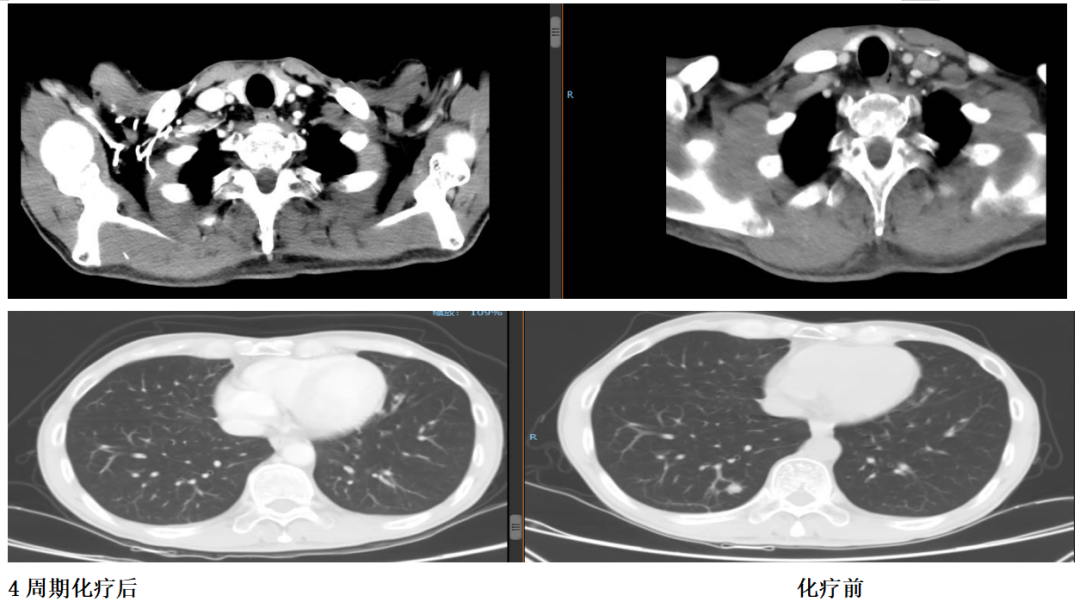

2018年8月10日复查胸部CT发现双肺多发小结节,遂定期观察随访。

2018年10月复查双肺结节较前增大。

同时发现左颈部和肝脏多发转移灶。

诊断:胃癌术后多发转移(双肺,肝脏,锁骨上淋巴结),Ⅳ期,HER2(+++)。

2018年10月23日至2019年2月3日行顺铂+氟尿嘧啶联合赫赛汀方案治疗5周期,疗效评估PR。

2019年1月24日,经4个周期赫赛汀+DF后,患者肝脏转移灶明显缩小。

2018年10月17日,化疗前

2019年1月24日,化疗后